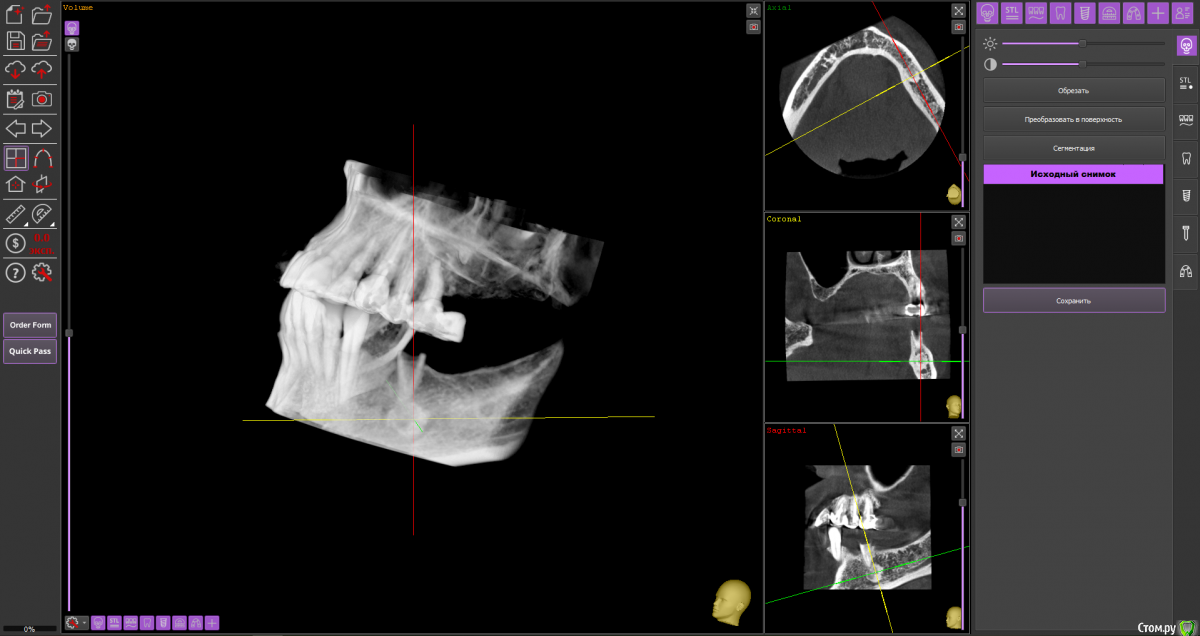

almaz7888 Опубликовано 11 февраля, 2021 Поделиться Опубликовано 11 февраля, 2021 (изменено) Доброе утро коллеги! Подниму тему. Данной пациентке планируется имплантация для замещения концевых дефектов на нижней челюсти. Зуб 3.5 думал удалить во время операции. Образование в области 3.5 это просто склероз кости? В области ментального отверстия справа также имеется какой-то очаг но меньших размеров. Изменено 11 февраля, 2021 пользователем almaz7888 Ссылка на комментарий